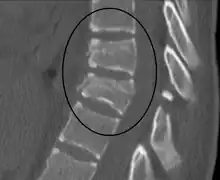

A Chance fracture of T10 and fracture of T9 due to a seatbelt during an MVC.

A Chance fracture is a type of vertebral fracture that results from excessive flexion of the spine.[8][9] Symptoms may include abdominal bruising (seat belt sign), or less commonly paralysis of the legs.[4][10] In around half of cases there is an associated abdominal injury such as a splenic rupture, small bowel injury, pancreatic injury, or mesenteric tear.[3][5] Injury to the bowel may not be apparent on the first day.[11]

The cause is classically a head-on motor vehicle collision in which the affected person is wearing only a lap belt.[2] Being hit in the abdomen with an object like a tree or a fall may also result in this fracture pattern.[12][10] It often involves disruption of all three columns of the vertebral body (anterior, middle, and posterior).[7][6] The most common area affected is the lower thoracic and upper lumbar spine.[6] A CT scan is recommended as part of the diagnostic work-up to detect any potential abdominal injuries.[5] The fracture is often unstable.[1]